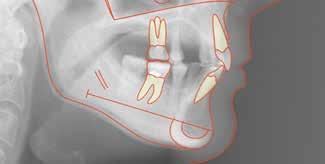

Patienttilfælde 1 (Fig. 1) er en 37-årig kvinde, henvist efter succesfuld behandling af stadie 3-parodontitis. Der er nu sundt

Før behandling

parodontium, ingen pocher over 4 mm, og både blødnings- og plakindeks er under 10 %. Patienten er motiveret for ortodontisk behandling, da hendes tænder er vandret over tid, delvist som følge af reduceret parodontium.

Der ses anterior trangstilling i begge kæber og overerupterede 1+1 og 2,1-1,2, hvilket resulterer i dybt bid med 2- tæt på ganepåbidning. Der er normale sidetandsrelationer, men der ses 5 mm horisontalt overbid (HOB) og 7 mm vertikalt

overbid (VOB). Papillen mellem 1+1 er betydeligt reduceret pga. fæstetab, og de mesialt kippede 1+1 har resulteret i en ”dark triangle”. Den facioorale funktion er for nuværende i.a. Panoramarøntgen (Fig. 1, I) viser marginalt knogletab i begge kæber og fravær af 8,7+7,8 og 8,7-8.

Objektivt anbefales behandling af det dybe bid, som ubehandlet forventes at forværres yderligere over tid. Patienten har ønske om behandling med æstetisk ortodontisk apparatur, alignere, og det vurderes muligt at behandle malokklusionen med alignere. Dog anbefales det generelt, at alignere undgås eller benyttes med væsentlige modifikationer af alignerens retention ved tandmobilitet, da dette ellers kan medføre jiggling, når aligneren tages af og på mange gange dagligt. På den anden side er der nogen evidens for, at alignerbehandling er associeret med bedre renhold og parodontal sundhed sammenlignet med fast apparatur (16).